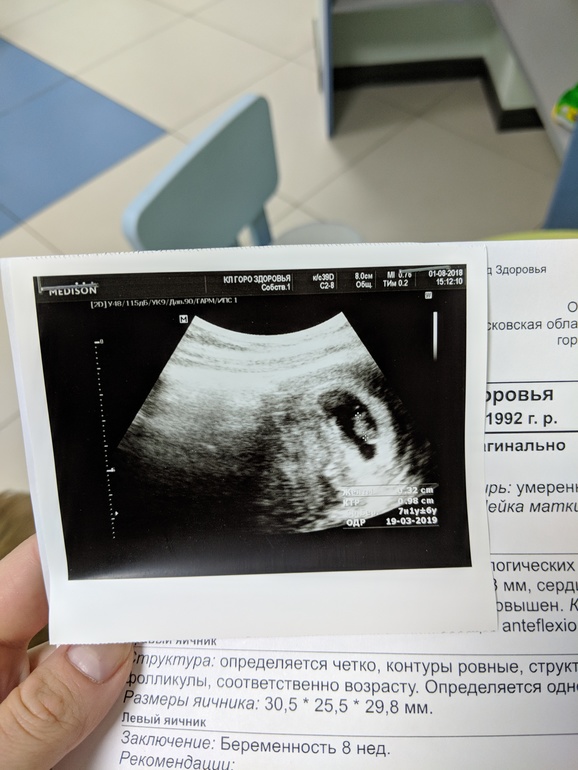

Смотрите...разница между УЗИ неделя и два дня.

Не маловаты ли показатели?...Смотрю,у всех ктр больше...

А врач не ошибся в описании кто в 8 Нед и 2 дня? Точнт9,8, а не 19,8? У меня 8,3 вчера было, на УЗИ поставили 8,4, ктр 18,9 мм.

На снимке УЗИ и срок по параметрам ктр стоит 7 Нед и 1 день. По меу вас 8,2 было,а в заключении она по параметрам поставила 8. А овуляция у вас когда была?

Ну у меня ПЯ ровно в 8 недель было 35 мм, КТР 18 мм, у вас поменьше. Я бы все равно не беспокоилась, все малыши по разному развиваются. По всем остальным параметрам у вас все в порядке, поэтому не заморачивайтесь.

У меня ктр на 8.4нед был 19.7мм